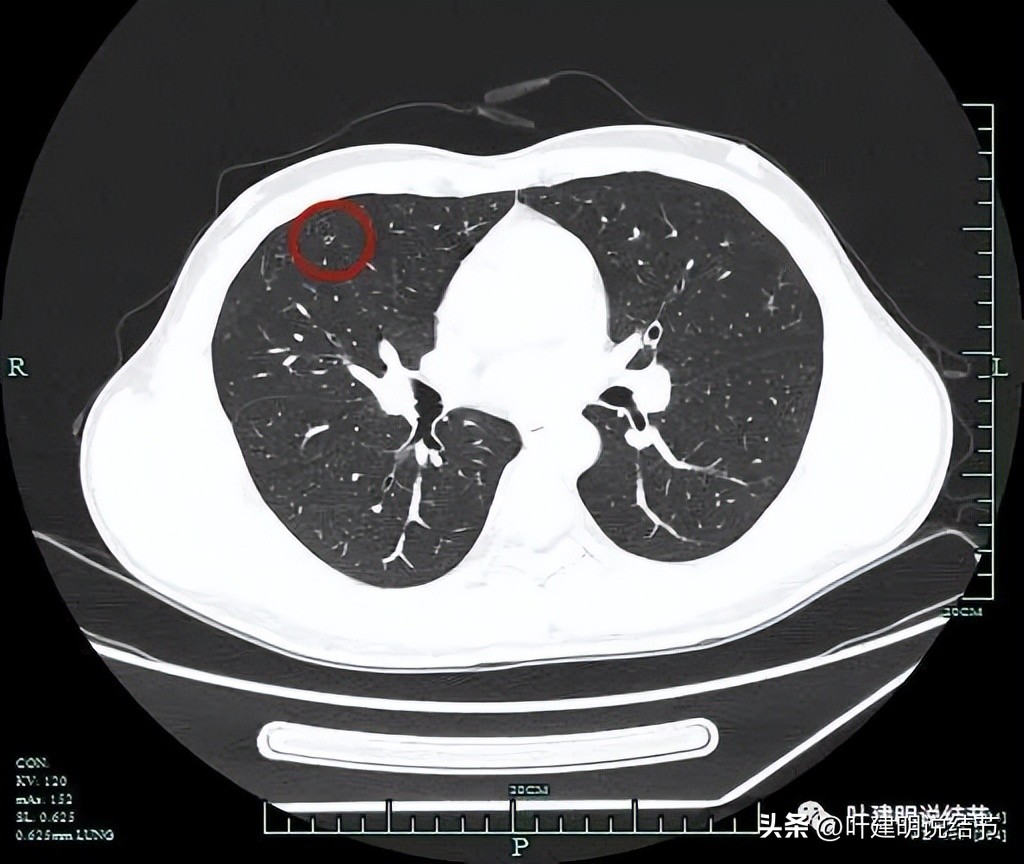

薄层平扫见三处病灶:

病灶1:右中叶磨玻璃结节,瘤肺边界与轮廓非常清楚,一看就是肿瘤范畴的结节,只是实性成分不明显,危险性可能还不算大。